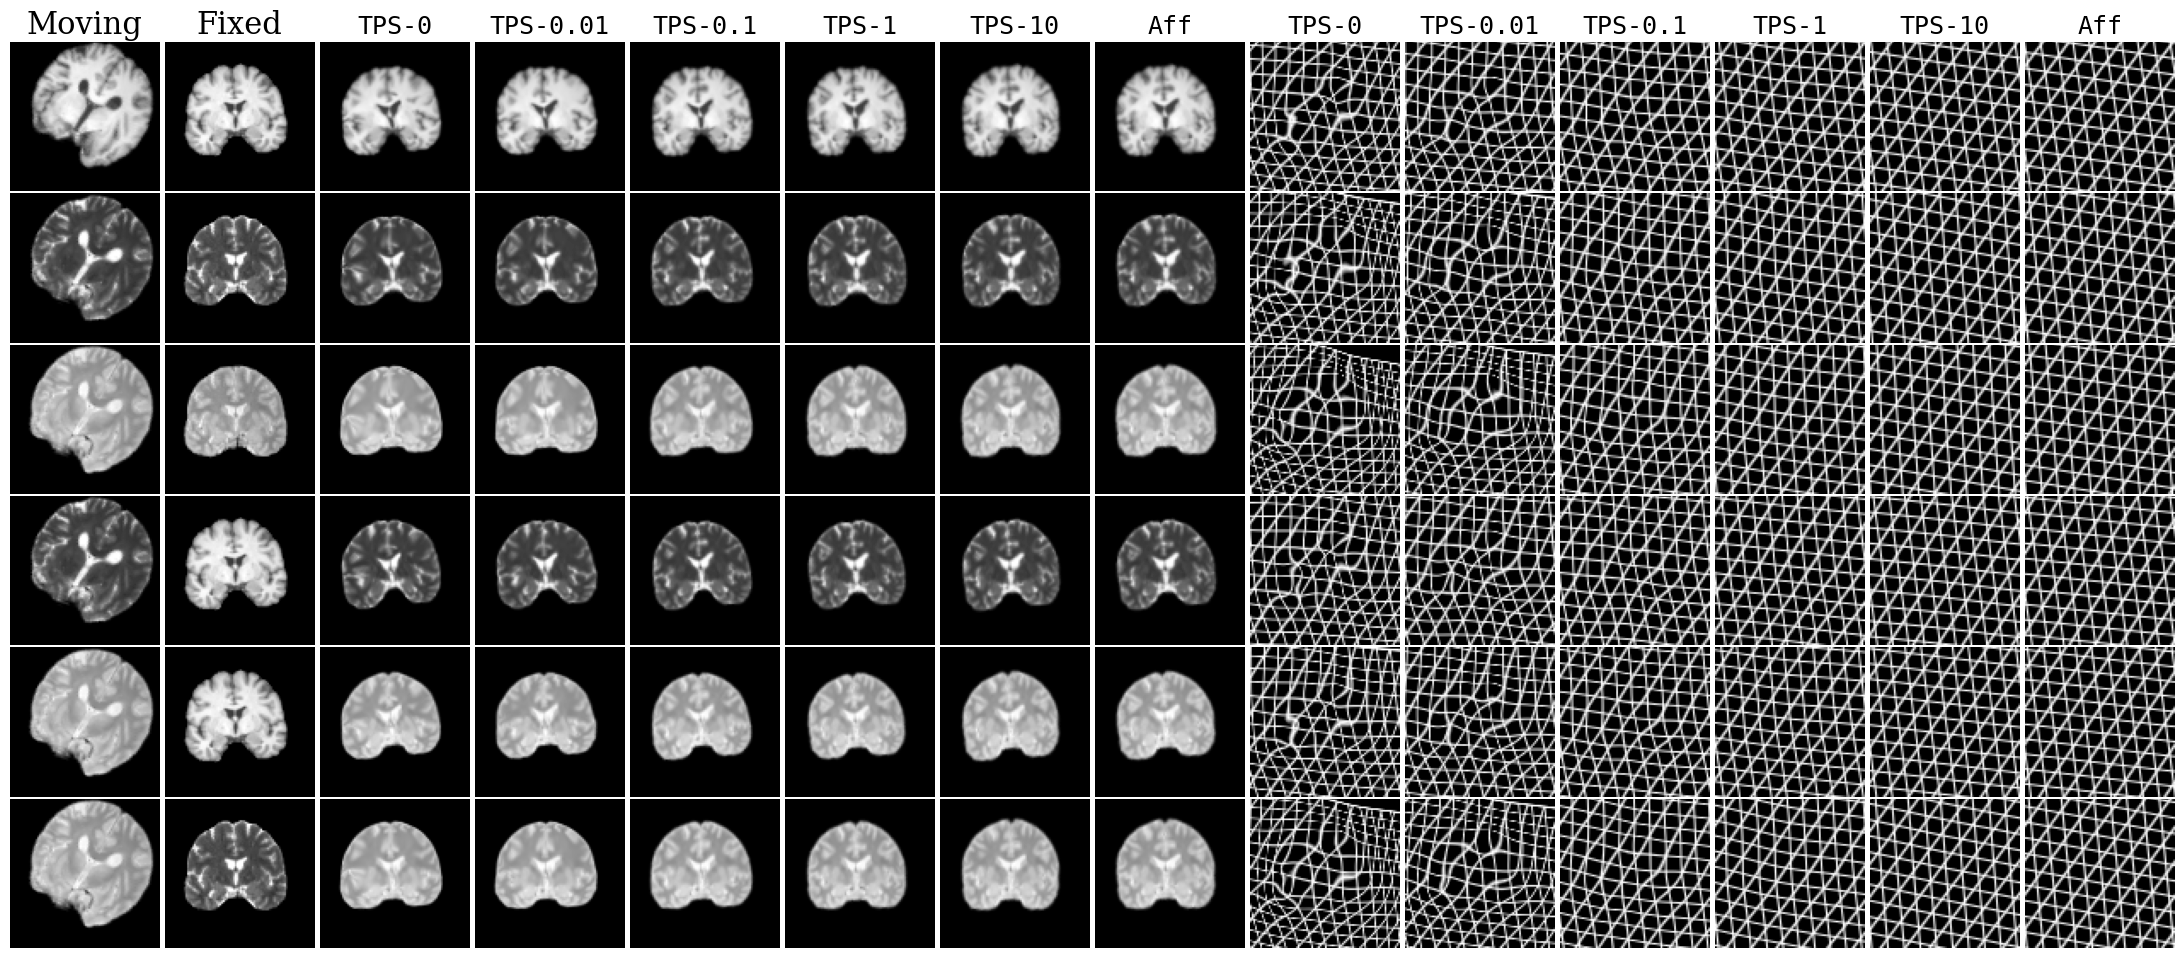

Refer to caption

Fig. 4: Representative registration results on different volumes from a pair of subjects, for unsupervised KM variants. Registered images are performed for different TPS λ𝜆\lambda’s and affine transformations. Deformed grids are depicted.

We provide qualitative results in Fig. 4, and compare the computational time across different models in Table 1. A comprehensive table of all methods and initial misalignments separated by modality are in Table 3. Additional metrics including Hausdorff distance and Jacobian-based metrics are presented in Fig. 16. Qualitative registrations for all models is provided in Fig. 17 and 18. Overall, the KeyMorph (KM) variants outperform other learning-based baselines, and KeyMorph performs comparably or often better (at large misalignments) than the state-of-the-art ANTs registration, while requiring substantially less runtime.